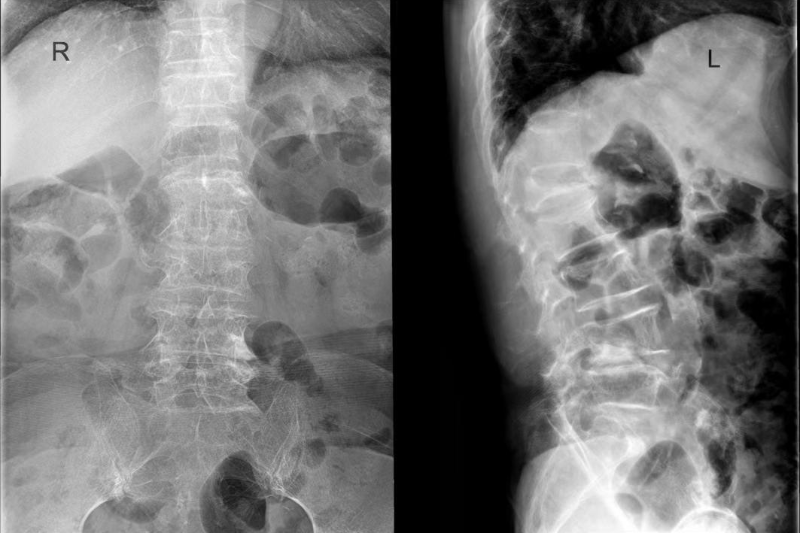

文章配圖

術前MRI:腰3/4、腰4/5椎間盤突出,伴椎管狹窄嚴重、神經根受壓、馬尾神經冗余。